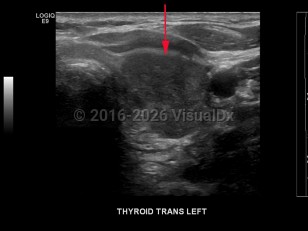

Signs and symptoms include a neck lump or swelling, neck pain, hoarseness, dysphagia, dyspnea, and/or persistent cough. Erythroderma may rarely be a cutaneous manifestation of malignancy.